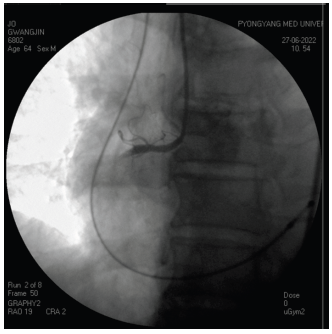

Treatment of Acute RVMI Complicated by High-Grade Bradycardia-Induced Shock Using Pacing-PTCA-ICT Combination

Jo Yong-Bong, Kim Song-Hwan, Kim Myong-Il, Ri Un-Hwa

43-46